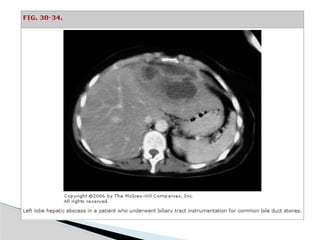

Computed Tomographic Scan

(Sensitivity 95%-100%)

 Well-demarcated areas hypodense to the

surrounding hepatic parenchyma.

 Peripheral enhancement is seen when IV contrast is

administered.

 Gas can be seen in as many as 20% of lesions.

 CT scan is superior in its ability to detect lesions less

than 1 cm.

 This technique also enables the evaluation for an

underlying concurrent pathology throughout the

abdomen and pelvis. Indium-labeled WBC scans are

somewhat more sensitive in this regard.